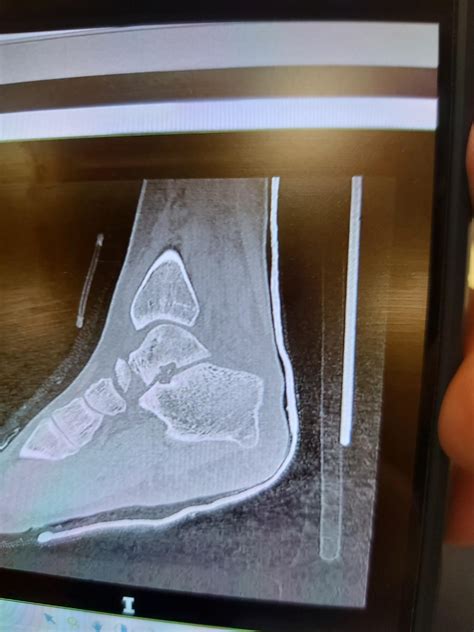

Ankle Instability in young Athletes | Zandu Fast Relief